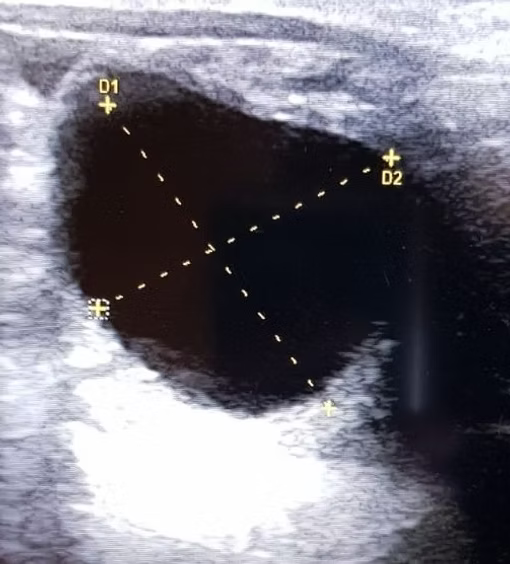

16 Tagen nach der künstlichen Besamung Ihrer Stute ist es möglich eine aussagekräftige Trächtigkeitsuntersuchung mittels Ultraschall durchzuführen. Hierbei ist es besonders wichtig eine Zwillingsträchtigkeit auszuschließen und den Besitzer über die weitreichenden Risiken aufzuklären. Dennoch ist es möglich, beim Vorliegen von zwei Fruchtanlagen eben nur einen gesunden Embryo heranwachsen zu lassen, um sowohl Stute, als auch Fohlen mit möglichst wenig Risiken auszusetzen. Die regelmäßige Untersuchung des Embryos ist bis zum dritten Trächtigkeitsmonat transrektal und später auch transabdominal durchführbar.